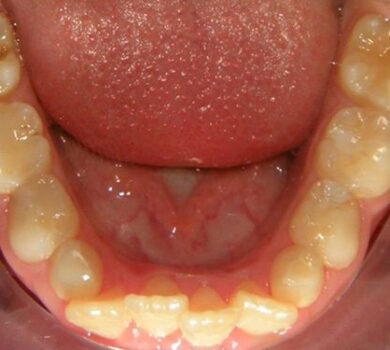

Si chiama Molar Incisor Hypomineralization (MIH) e, se non diagnosticata precocemente ed intercettata, può portare a quello che